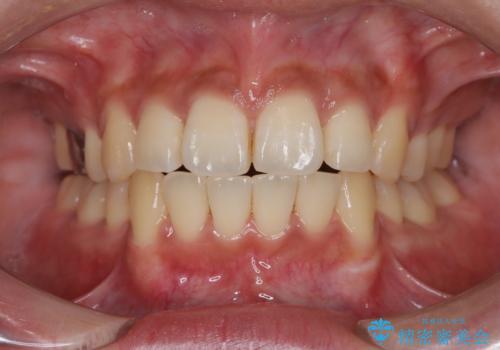

前歯が前に出ているため口元が突出し、唇が閉じにくいなどの悩みを抱えておられました。治療にあたり上下左右の第一小臼歯を抜歯し、十分なスペースを作ることで前歯を効果的に後方へ移動させました。装置には透明で目立ちにくい審美ブラケットを採用し、治療中の審美的ストレスを軽減しました。定期的な調整を通じて無理なく確実に歯列を整え、前歯の突出感を解消。治療後は口元の印象が自然で美しく改善され、患者様には非常にご満足いただけました。